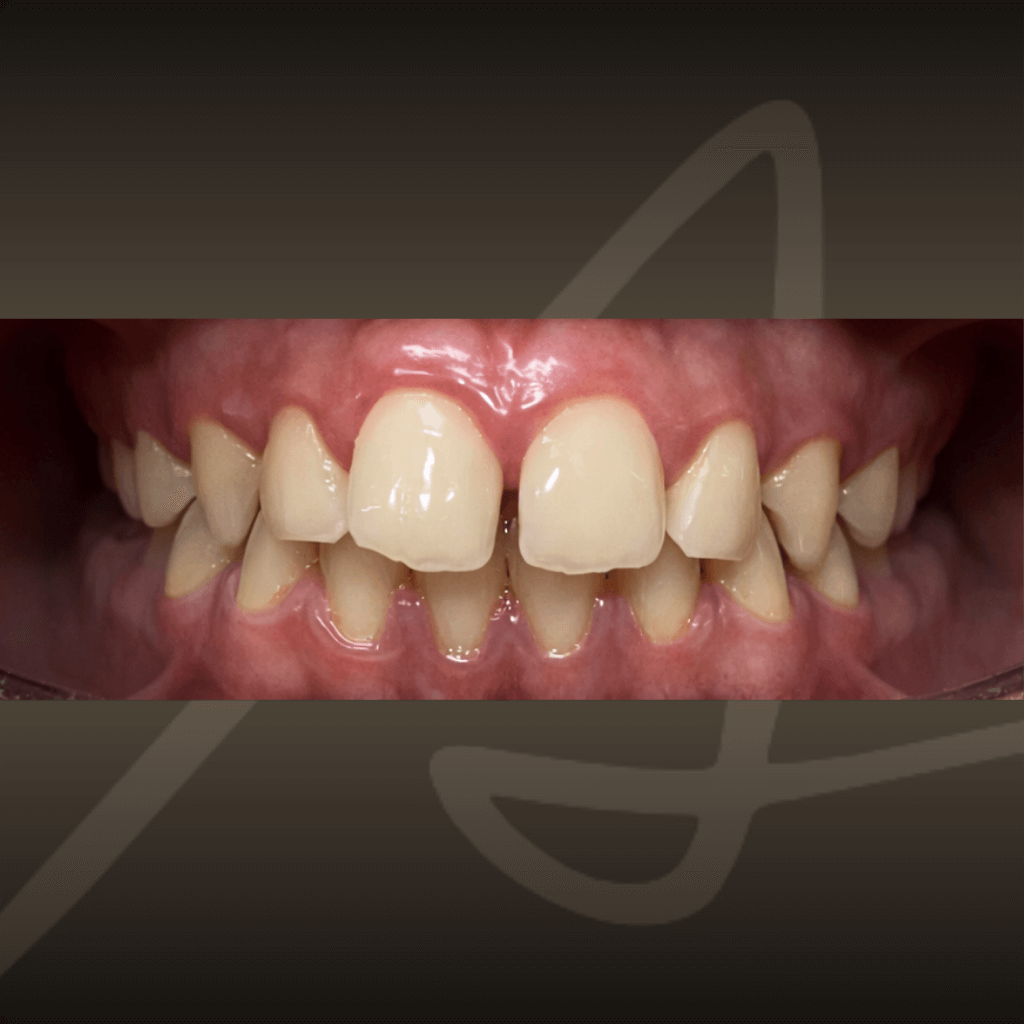

Ортодонтията не е само въпрос на подредба. Правилното лечение подобрява захапката, речта и създава стабилна основа за дългосрочно дентално здраве. Независимо от възрастта, ортодонтското лечение може да допринесе за по-добър функционален баланс и по-лесна поддръжка на зъбите във времето.